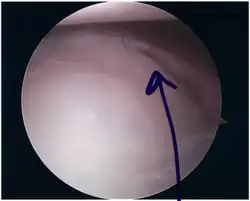

Als Bankart-Läsion wird eine spezielle Verletzung (Läsion) des Schultergelenkes bezeichnet, die in der Regel durch eine Ausrenkung der Schulter (Schulterluxation) nach vorn bei einem Trauma verursacht wird. Dabei ist die Gelenklippe (Labrum glenoidale) der Gelenkpfanne (Cavitas glenoidalis, auch kurz Glenoid) des Schulterblatts im unteren Bereich des vorderen Pfannenrandes teilweise oder vollständig abgerissen.

Bei einer Bankart-Läsion kann im Bereich des Abrisses die Gelenklippe das Schultergelenk nicht mehr richtig stabilisieren und es kann leichter zu einer (weiteren) Ausrenkung der Schulter kommen (besonders in Verbindung mit einer Hill-Sachs-Läsion).